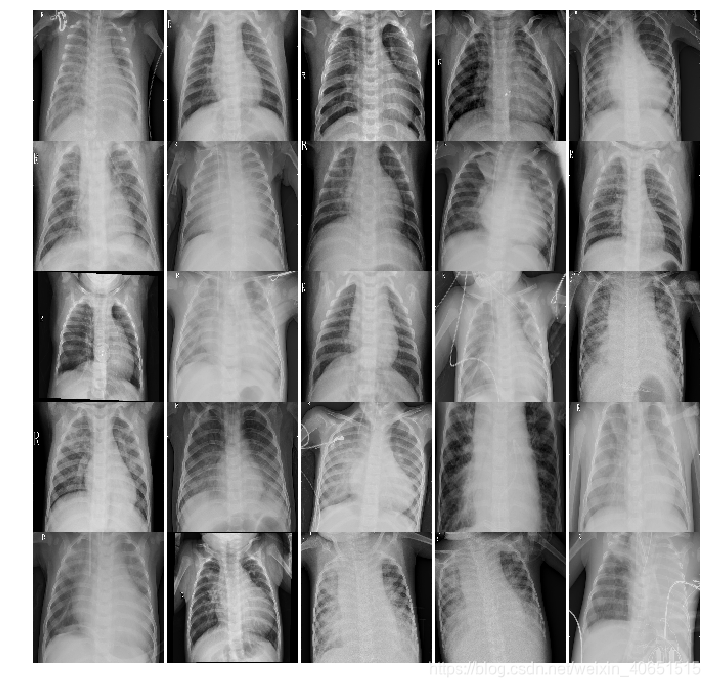

数据集样本展示:肺炎样本X-ray图像和正常X-ray肺部图像

肺炎X-ray图像: